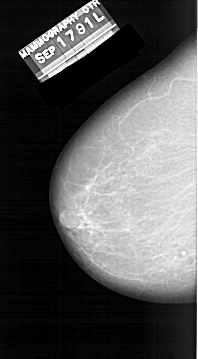

A_1309_1.LEFT_MLO

A_1309_1.LEFT_CC

LEFT_CC LINES 5731 PIXELS_PER_LINE 3166 BITS_PER_PIXEL 12 RESOLUTION 43.5 NON_OVERLAY

LEFT_MLO LINES 6871 PIXELS_PER_LINE 3496 BITS_PER_PIXEL 12 RESOLUTION 43.5 NON_OVERLAY